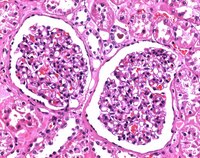

| Application | (approx. 10% Formalin solution) for histology |